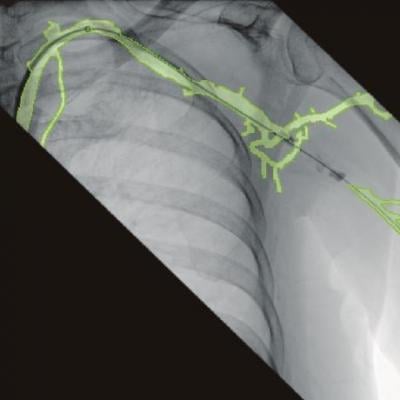

An example of the 3-D vascular roadmapping technology on the Ziehm mobile C-arm systems.

Founded in 2007, Therenva supports physicians in planning and performing minimally invasive endovascular interventions through innovative imaging solutions. The current portfolio includes EndoSize and EndoNaut, a patented solution for intra-operative 3-D navigation and localization of devices providing more confidence, accuracy, and visual comfort during catheterization procedures.

By bundling the leading C-arms of Ziehm Imaging and the EndoNaut solution, physicians already benefit from advanced 3-D intra-operative navigation for optimal guidance in endovascular interventions.

“Joining forces with Ziehm Imaging as innovation leader in mobile C-arm technology is a great opportunity for us to make our software devices available to physicians globally,” said Cemil Göksu, Co-founder and CEO of Therenva. “A deeper soft- and hardware integration will allow us to develop solutions that will set new standards in image fusion and 3-D navigation to provide clinicians with powerful yet seamless workflows supporting their patients’ treatment.”